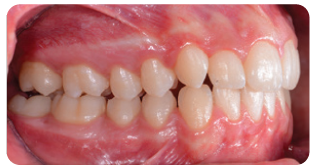

After four months of the Carriere Motion Appliance and full-time intermaxillary elastics, a Class I molar and canine relationship was achieved.

To avoid relapse, we started clear aligner therapy less than two weeks after the Carriere Motion Appliance was removed. The virtual setup showed that 12 aligners would be needed in each arch to resolve the crowding and achieve leveling and alignment.